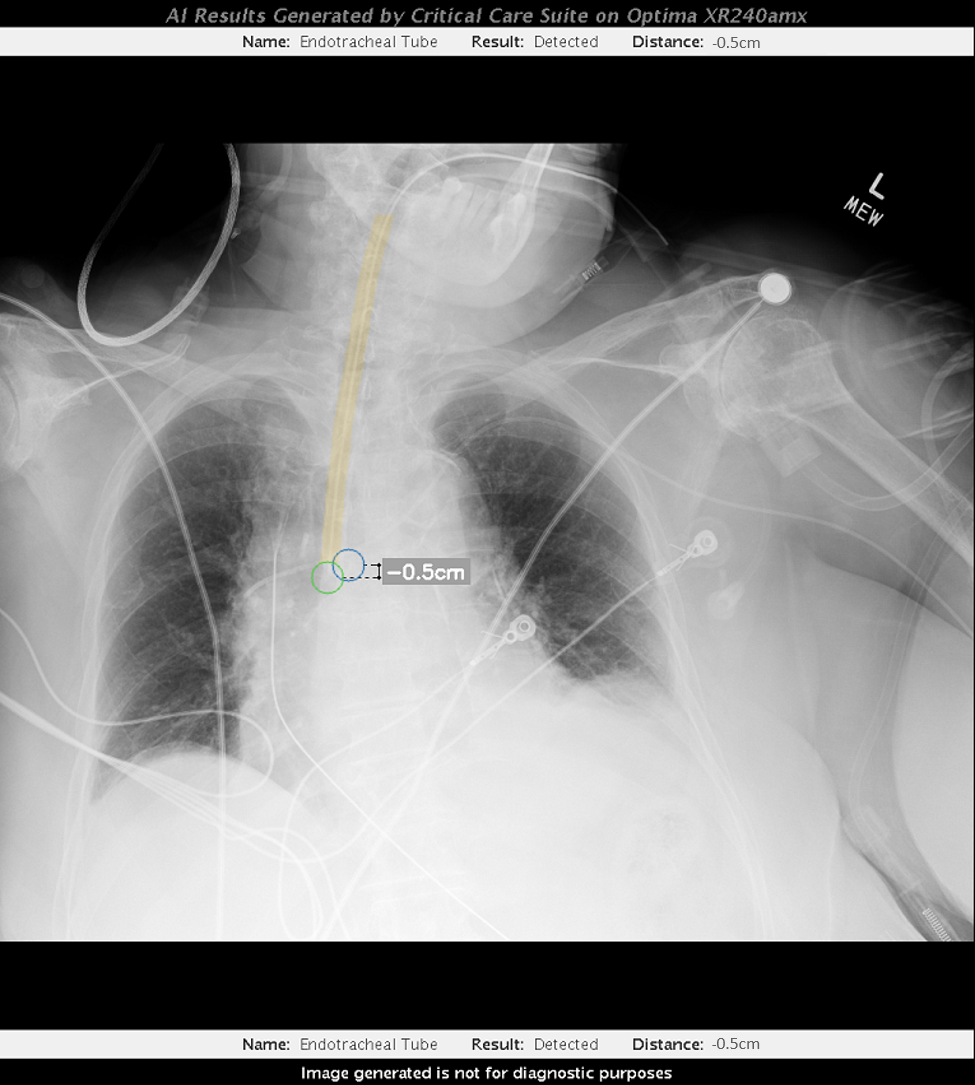

Top and above images: A radiologist reads an X-ray scan using GE Healthcare’s Critical Care Suite 2.0 — a collection of algorithms embedded in mobile X-ray devices that give hospitals access to AI without huge investments in IT infrastructure. Images credit: GE Healthcare.

GE’s AI detects the end of the tube, calculates its distance from the carina and displays the data on the X-ray monitor within seconds of capturing the image. That instantaneous feedback can help give clinicians more confidence in their work and help identify which patients need additional adjustment.